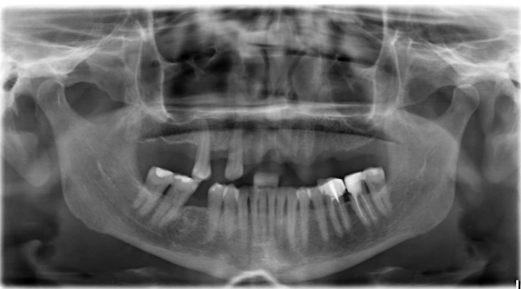

After intra oral examination and radiological reviews (panoramic radiograph and cone beam computer tomography scan) It was observed that the width and height of alveolar bone is not enough for classic implant placement, as a result the choice of appropriate implant is important fig 6.

With bone width of 5 to 6 mm One piece Tissue level implants (ROOTT, TRATE AG) were the implants of choice.

Figure 6